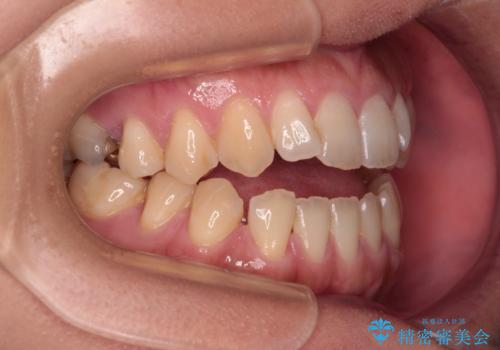

【モニター】食事が取りづらい 極端な開咬をインビザラインで解決

- 極端な開咬を気にして来院された患者様です。

開咬の方の特徴として、幼少期の指しゃぶりの癖や、強い舌の突出癖が挙げられます。

こちらの患者様も強い舌の突出癖が認められたため、矯正治療を行うにあたり、舌のトレーニングをしっかりと行っていただくように指示をいたしました。

開咬はインビザラインが得意とする歯列不正であるため、舌のトレーニングを行いながら、インビザラインにて矯正治療を行うこととしました。

担当医としては、もっと上下の前歯を接触させるところまで治療を進めたいという思いがありますが、今まで咀嚼できなかったものが食べられるようになったということで、この状態で治療終了となりました。